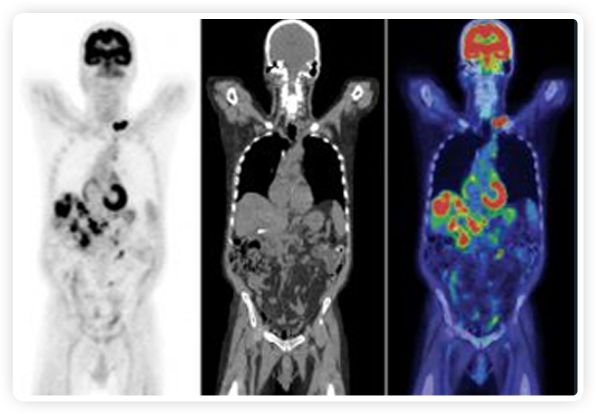

到目前為止,放射腫瘤學(xué)中(使用的圖像主要是結(jié)構(gòu)性的,而PET圖像可以提供生物學(xué)信息。通過使用注射示蹤劑,例如18-FDG,PET可以描繪腫瘤的代謝活性,使其“點(diǎn)亮”。(FDG是用于可視化癌癥代謝的最廣泛使用的示蹤劑。與正常組織相比,腫瘤細(xì)胞保留更高水平的FDG。)不同的PET示蹤劑可以識別腫瘤的不同生物學(xué)特征,例如特定生物標(biāo)志物抗原(例如,PSMA)或甚至探測免疫系統(tǒng)本身(例如,PDL1表達(dá)或活化的T細(xì)胞)。

RefleXion將PET成像與立體定向放射治療相結(jié)合。在注射示蹤劑后,RefleXion的技術(shù)基于示蹤劑信號實(shí)時地在一個或多個目標(biāo)上引導(dǎo)治療性X射線。使用這種專有方法,RefleXion的平臺有可能比現(xiàn)有系統(tǒng)向癌癥病變提供更高劑量的輻射,并改善周圍健康組織的保護(hù)。